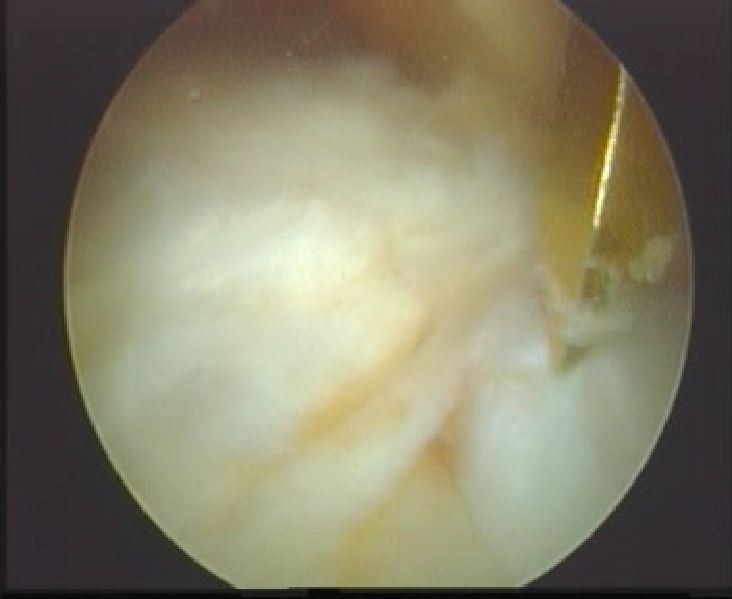

关节镜下观

正常前交叉韧带

前交叉韧带损伤后形成的疤痕组织